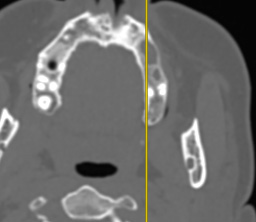

Визуализация костных структур средней трети лица по данным МСКТ имела погрешности ввиду фонового ответа на наличие инородных тел в полости рта (ортопедические конструкции), что вызывало ряд вопросов к состоянию соединительнотканных структур (рис. 3).

Рис. 3. Пациентка Э., предоперационное МСКТ, вид ВЧП слева

Данные КЛКТ позволили детализировать нюансы зубочелюстной системы, в частности корней зубов, которые являлись причиной патологического процесса в полости ВЧП (рис. 4).

Рис. 4. Пациентка Э., предоперационное КЛКТ, вид ВЧП слева

Возможности реформатора КЛКТ позволили визуализировать максимальное количество сечений ВЧП и окружающих ее структур для дифференциальной диагностики и последующего успеха оперативного вмешательства (рис. 5).

Рис. 5. Пациентка Э., предоперационное КЛКТ, вид ВЧП слева